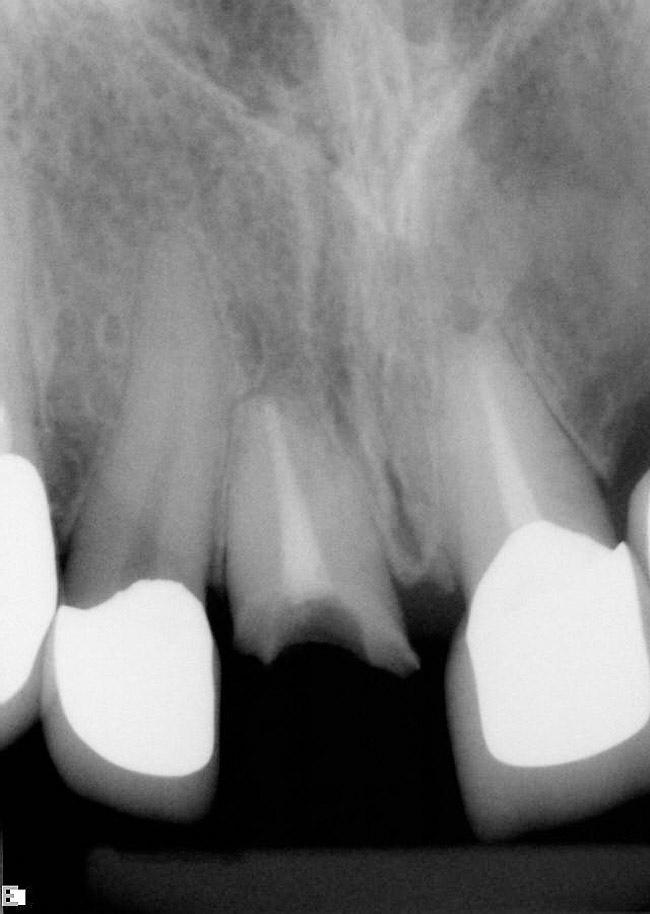

Immediate provisional restoration of a complete crown fracture

From www.styleitaliano.org

Immediate provisional restoration of a complete crown fracture Which Provisional Crown Is Preferred For An Anterior Tooth Capability of retaining the provisional crown for months,. Dental procedures that may require provisional coverage. during fabrication of a custom acrylic provisional crown which dental laboratory instrument is used to polish the crown? an ideal provisional cement should exhibit the following characteristics: the resin and shell then become a single bonded unit, providing the patient with strength. Which Provisional Crown Is Preferred For An Anterior Tooth.